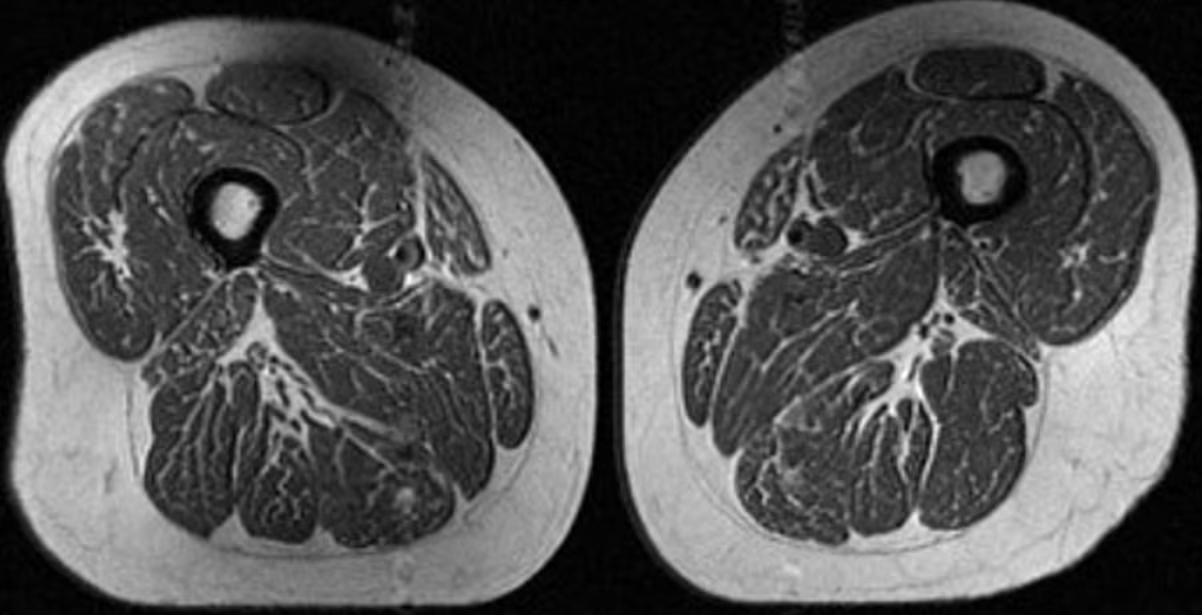

Η εικόνα που εξετάζουν οι ερευνητές δεν είναι ωστόσο φαγητό. Πρόκειται για μαγνητική τομογραφία (MRI) του μηρού μιας 62χρονης γυναίκας, η οποία αντλούσε το 87% των ετήσιων θερμίδων της από υπερεπεξεργασμένα τρόφιμα.

Η γυναίκα με 87,1% υπερεπεξεργασμένα τρόφιμα στη διατροφή της (A στην εικόνα παρακάτω) είχε BMI 32,6 και χαμηλότερη φυσική δραστηριότητα από τη δεύτερη γυναίκα (B στην εικόνα), η οποία είχε BMI 31,8 και 29,5% υπερεπεξεργασμένα τρόφιμα. Παρ’ όλα αυτά, η πρώτη εμφάνιζε πολύ πιο έντονη λιπώδη διήθηση στους μηρούς.